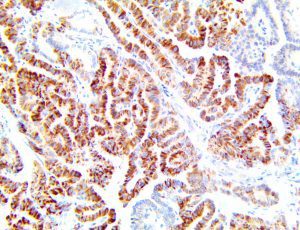

The first cytokines released are interleukin 1β (IL-1β) and tumor necrosis factor-α (TNF-α), which attract a variety of circulating white blood cells (WBCs) to the infection site, including neutrophils, monocytes, macrophages, and natural killer (NK) cells. This response, along with the antipathogenic chemicals released by these cells (i.e., complement), comprise the innate immune response. These cells directly attack the invading pathogen and also release additional cytokines, chief among them interleukin-1 and 6 (IL-6). IL-6 is essential for invoking the adaptive immune response, which calls T-cells, B-cells, and T helper (Th) cells to the infection site. IL-6 also stimulates further recruitment, proliferation and activation of macrophages.

This activation induces inflammatory monocytes to highly express IL-6, starting a localized and then systemic cascade effect that results in hyperproduction of IL-6, which accelerates the inflammatory process. Because IL-6 also increases vascular permeability, excessive levels cause blood vessels to become very leaky. This, along with clotting factors released from vascular endothelial cells, stimulates the coagulation cascade, resulting in microthrombosis (tiny clots), which leads to ischemia and tissue death of the kidney, intestines, heart, liver, brain and extremities.